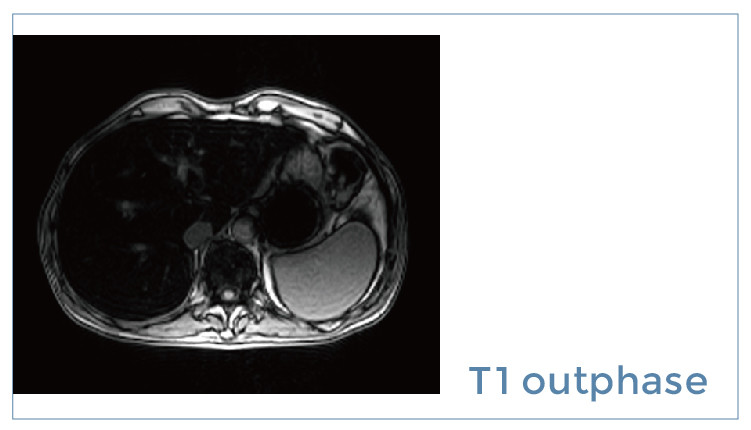

【朗润影像档案】磁共振影像病例分享(编号20190914)